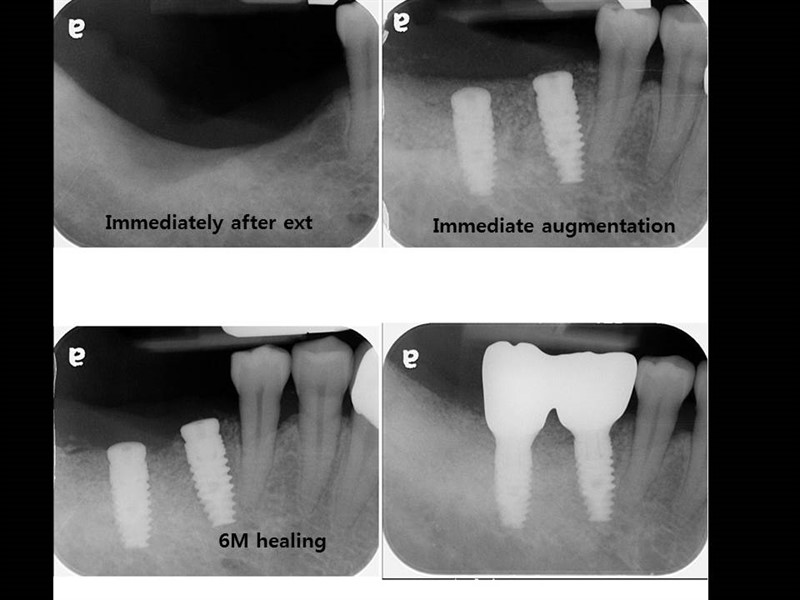

Етапи імплантації зубів

Імплантація зубів – процедура, що вимагає суворого дотримання встановленого протоколу лікувально-діагностичних заходів, що включає кілька етапів імплантації зубів. Кількість і характер етапів імплантації можуть відрізнятися в залежності від початкового стану зубощелепного апарату пацієнта, а також обраного виду і методики проведення самої процедури установки імплантів – одно або двоетапної.

Двоетапна методика є найбільш надійною і прогнозованою, вона відрізняється дуже високими показниками приживлюваності імплантатів (97-98%), а встановлені з її використанням штучні зуби можуть прослужити 15-20 років, а нерідко і довше. Процедура встановлення дентальних імплантів по двоетапній методиці можна виділити 3 основних етапи імплантації:

На цьому етапі імплантації здійснюється установка самого імпланту і формувача – перехідника між кореневою частиною імпланта і його супраструктурами. Таким чином, в хірургічному етапі можна виділити два проміжних етапу імплантації:

При використанні класичної двоетапної методики імплантації спочатку встановлюється сам імплант і лише після його повного і остаточного приживлення на ньому через перехідник (формувач) фіксується супраструктура – коронка або міст. Проміжок між цими двома етапами імплантації становить кілька місяців.

Десна надрізається по гребеню альвеолярнго відростка і відшаровується слизисто-окисний клаптик, щоб створити необхідне поле для роботи хірурга-імплантолога. Далі за допомогою фрез різного діаметру (від меншого до більшого) висвердлюється канал потрібного діаметру і глибини – формується кісткове ложе для штучного кореня. У це ложе встановлюється імплант на необхідну глибину: гвинтові конструкції вкручуються, циліндричні встановлюються незначною натяжкою.

Коли імплант встановлений, в нього вкручують заглушку, яка захищає його від механічних впливів, а також запобігає інфікуванню кісткового ложе і проростання тканин в отвір для гвинта. Після цього слизисто-окисний клаптик укладається на своє колишнє місце, а розріз щільно зашивається. На цьому перший хірургічний етап імплантації закінчується.

Далі йде «перерва», необхідна для надійного приживлення імпланта. Кісткова тканина нижньої щелепи, більш щільна і об’ємна, для цього потрібно 2-3 місяці, в менш щільній губчастій кістці верхньої щелепи він приживається 4-6 місяців.

Коли коренева частина імпланта надійно прижилася, на неї встановлюється формувач, вірніше два його різновиди, які ставляться по черзі. Спочатку встановлюється абатмент, що виконує роль формувача ясен, щоб створити її чіткий рівний контур, не відрізняється від ясенного краю «рідних» зубів. Для цього замість заглушки встановлюється формувач ясен, який виступає над нею на кілька міліметрів. Формування ясенного краю сягає близько 2 тижнів.

Через 2 тижні формувач ясен видаляється і на його місце встановлюється постійний абатмент. За допомогою абатмента можна буде при необхідності відрегулювати довжину коронкової частини імпланта і кут його нахилу. Для цього використовуються абатменти різної довжини і з різним кутом нахилу, що дозволяє максимально точно «вписати» імплант в зубний ряд.